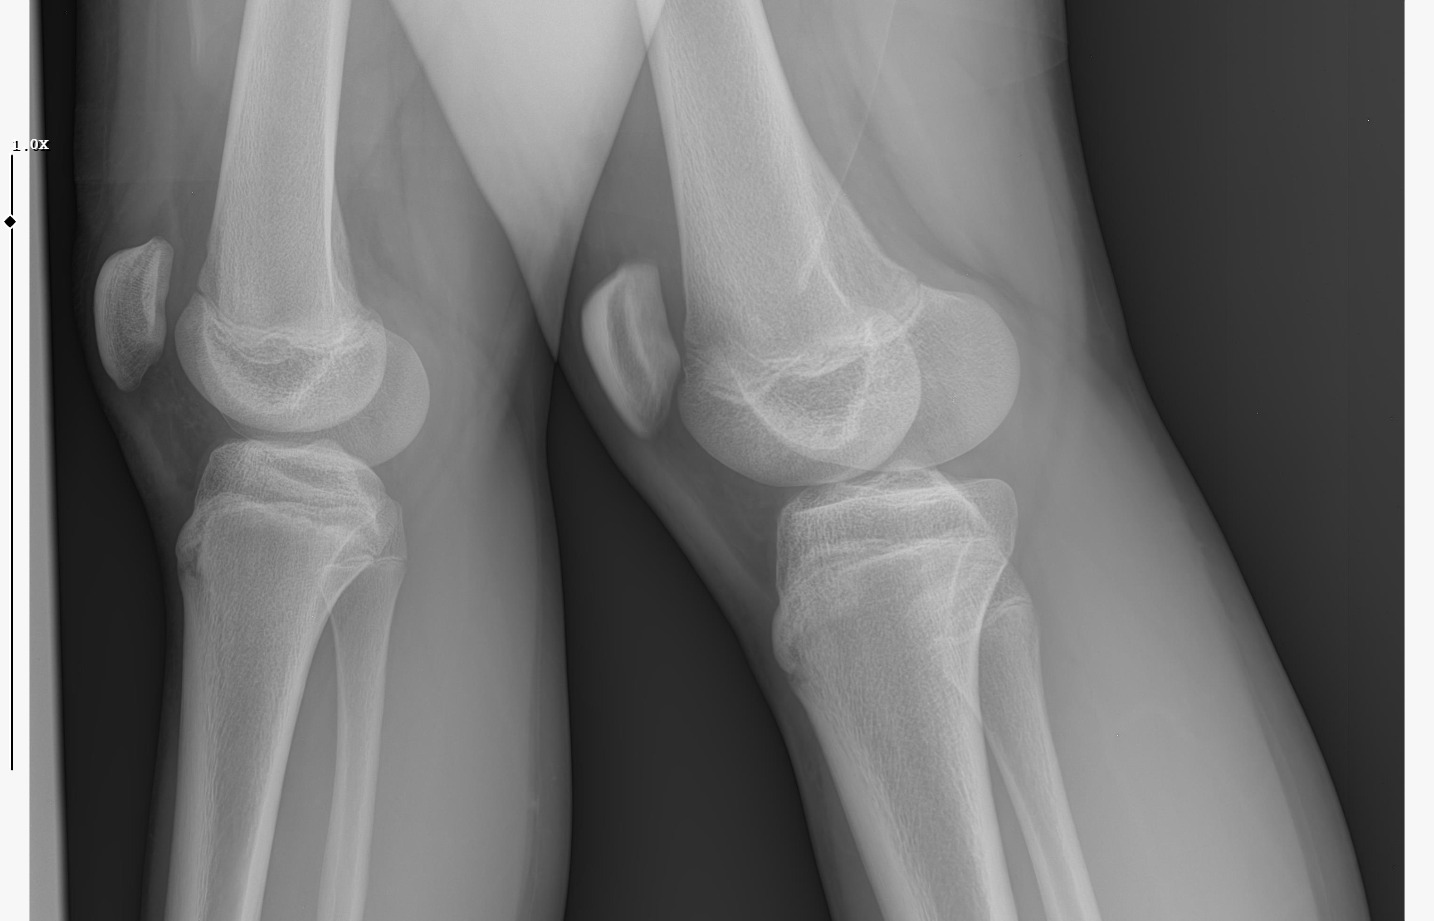

doktor bi sik bilmiyodur büyük ihtimalle plakları buraya at biz bakak

röntgeni atar mısın?

• WhatsApp Image 2026-01-07 at 00.31.08.jpeg

WhatsApp Image 2026-01-07 at 00.31.08.jpeg

138.6 KB · Views: 0

kapanmaya baslamıs ama cok yakın degil

kemik yaşın 15 gibi 15'e çok yakın

anne baba boyun ve yaşını bilmiyorum sadece bu bilgilerle 171-175 arası diye tahmin ediyorum röntgen ile.

normalde anne babana göre 171-176 olman gerek zaten. kemik yaşın ve şuanki boyun ile yapılacak tahmin anne baban ile yapılabilecek tahminle nerdeyse birebir aynı yani büyük ihtimal o civarlar olursun bence